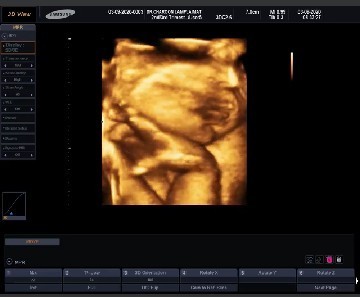

30 สัปดาห์

แม่ๆว่าน้องจะออกมาน้ำหนัก3000กว่ามั้ยคะ ไปซาวด์มาหมอไม่บอกน้ำหนักเลยค่ะกังวนว่าลูกจะน้ำหนักน้อย

ในใบซาวด์มันมีน้ำหนักแจ้งนะคะ